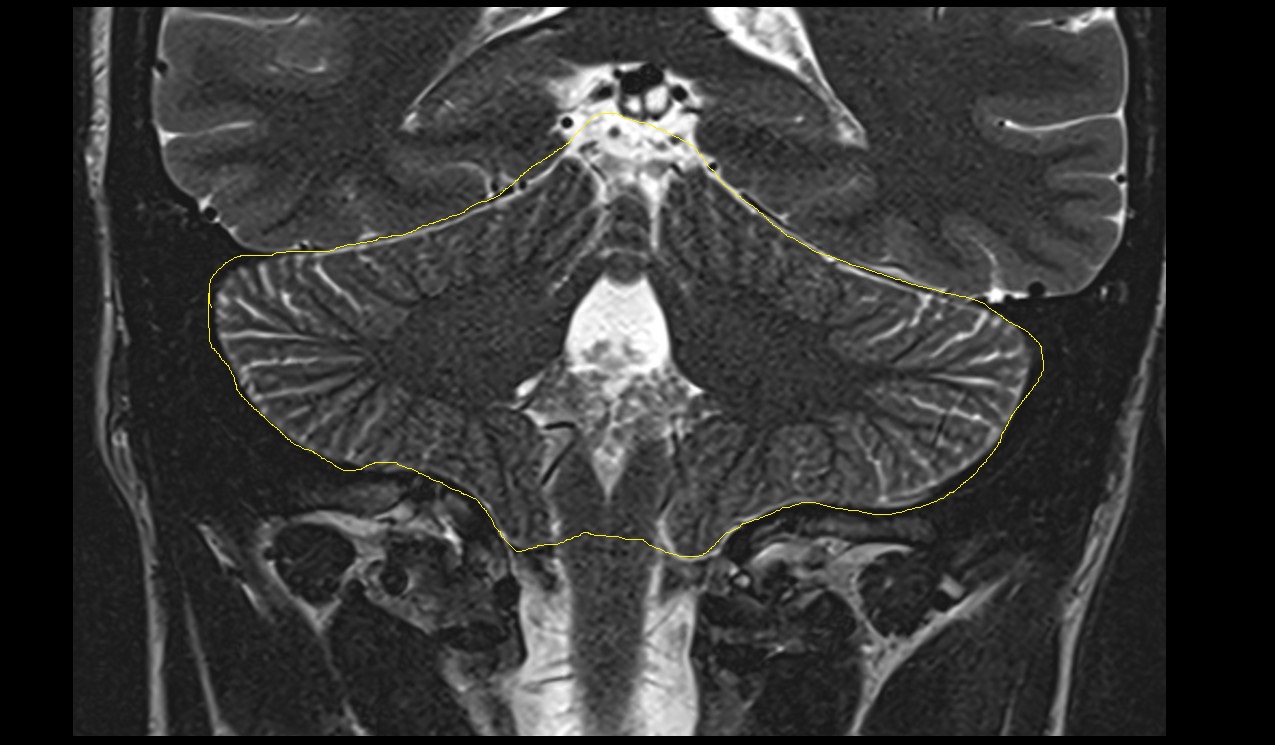

- Cerebellum

- Crus I of ansiform lobule of cerebellum

- Crus II of ansiform lobule of cerebellum

- Paramedian lobule (HVII) of cerebellum

- Simple lobule (HVI) of cerebellum

- Anterior quadrangular lobule (HV) of cerebellum

- Anterior quadrangular lobule (HlV) of cerebellum

- Biventral lobule (HVIII) of cerebellum